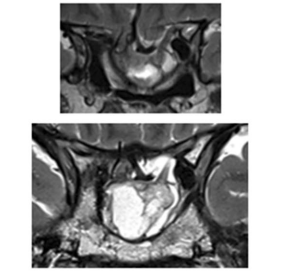

图1:初始病灶

图:影像显示第一次肿瘤切除8年后复发,并伴有脑出血和鞍底下陷

第二次手术后MRI,显示肿瘤残余,继发性空蝶鞍综合征伴有鞍区前交通动脉复合体的下移位。